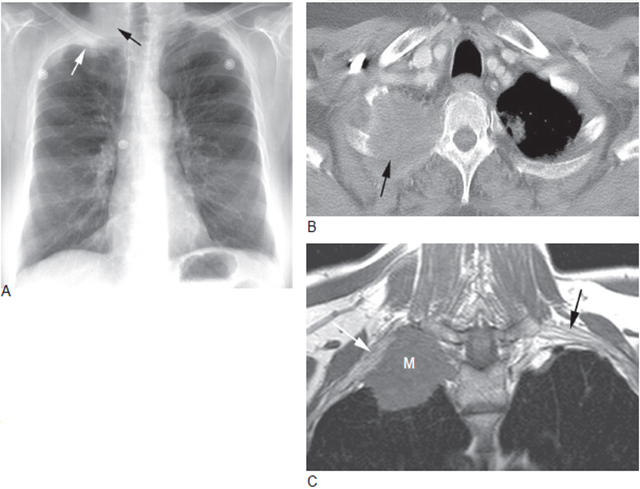

图5 肺上沟瘤显示胸膜帽,伴骨破坏和臂丛神经受侵

A. 右肺尖肺上沟瘤(白箭头) 与胸膜增厚类似,下方的肋骨可见部分破坏(黑箭头);B.CT 显示右肺尖占位性肿块,局部肋骨破坏(箭头);C.MRI 的T1WI 示右肺尖肿块,臂丛神经受累(白箭头),左侧臂丛神经正常, 可资对照